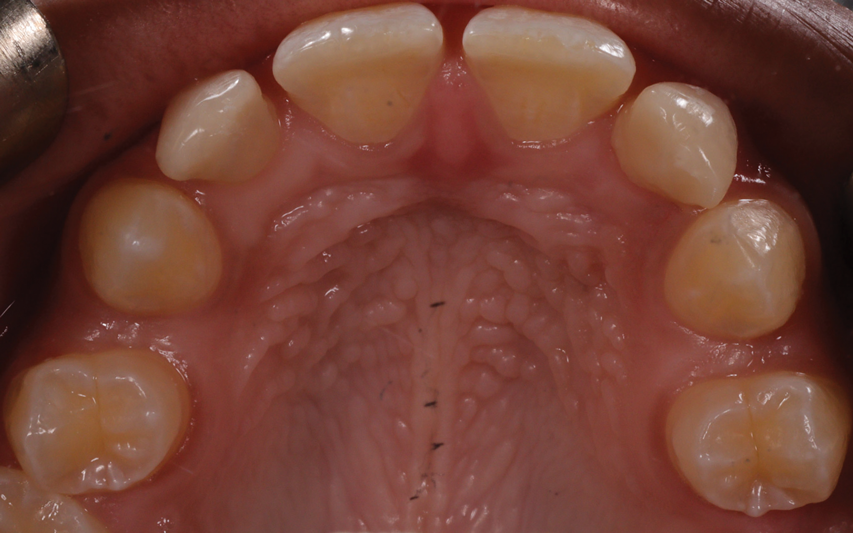

A 16-year-old female patient presented with the chief complaint that she was dissatisfied with the appearance of her anomalous maxillary lateral incisors (teeth Nos. 7 and 10) and multiple diastemas (Figure 1 through Figure 4). She had been referred for restorative treatment after an initial consultation with the orthodontist. Her first restorative appointment was dedicated to data collection, which included a health history and physical examination as well as the acquisition of photographs (facial, dentofacial, dental), videos (chief complaint, F sound, S sound), vinyl polysiloxane (VPS) impressions, a panoramic radiograph, a bite registration, and a facebow registration. The clinical examination revealed that both of the patient's maxillary lateral incisors were peg-shaped. After a discussion about the risks and benefits of different treatment options, such as direct composite restoration, indirect composite veneers, and porcelain laminate veneers, she chose to have her maxillary lateral incisors treated with direct composite buildup restorations. The index cutback technique was chosen for this case instead of a freehand technique in order to create a new shape according to an ideal wax-up but also to be able to control the thickness of the enamel layer.7

(4.) Pretreatment retracted occlusal photograph showing the multiple diastemas.

Figure 4